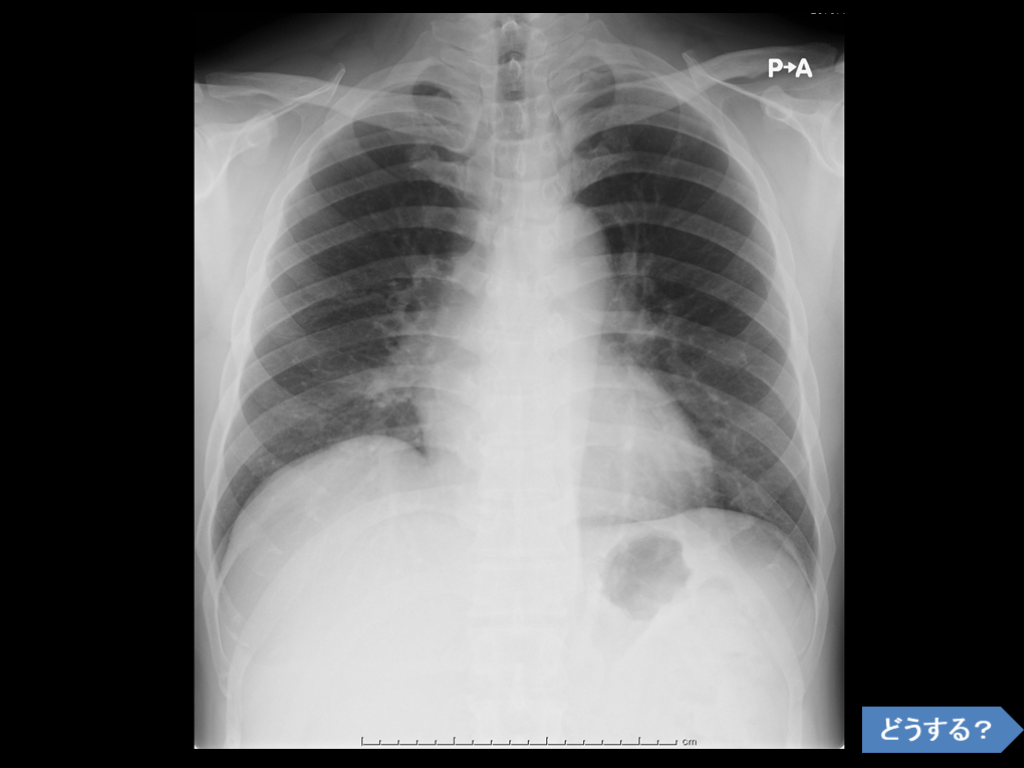

Question break : 66歳女性 咽頭違和感 BP 142/85mmHg, 91/min reg 意識清明でsickではない、呼吸促迫なし 視診・触診で頚部に明らかな異常を認めない 脳神経: 眼球運動np 上部/下部顔面筋 np   舌運動ok 顔面感覚 np 【L/D】 CBC 特記事項なし WBC上昇なし 電解質、腎・肝機能問題なし CK上昇なし 【頭部CT】  特記事項なし 【胸部CT】  左乳腺にsoft tissue density mass 乳癌の疑い

帰宅させられそうだが、見直すと‥ 突発性咽頭違和感で発症した大動脈解離